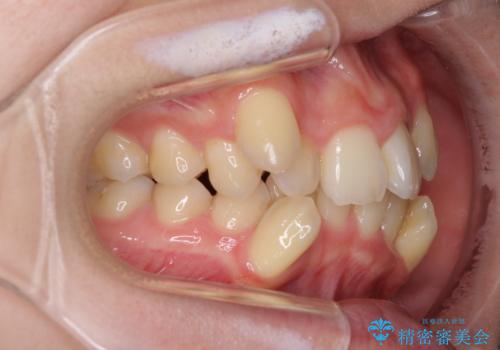

- 上下の八重歯や乱杭歯を気にして来院され患者様です。

スペースを確保するため、上下左右の第一小臼歯を抜歯し、ワイヤー装置に矯正することとしました。